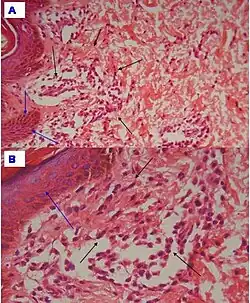

Urticaria pigmentosa is characterized by excessive amounts of mast cells in the skin. Red or brown spots are often seen on the skin, typically around the chest, forehead, and back. These mast cells, when irritated (e.g. by rubbing the skin, heat exposure), produce too much histamine, triggering an allergic reaction that leads to hives localized to the area of irritation, sometimes referred to as Darier's sign. Severe itching usually follows, and scratching the area only serves to further symptoms. Symptoms can be mild (flushing and hives that require no treatment), moderate (diarrhea, tachycardia, nausea/vomiting, headache, and fainting), or life-threatening (vascular collapse requiring emergency treatment and hospitalization).